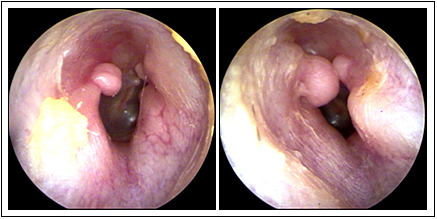

JFC Poliposis nasal

JFC Poliposis nasal simple

JFC Poliposis nasal.

JFC Poliposis nasal bilateral.